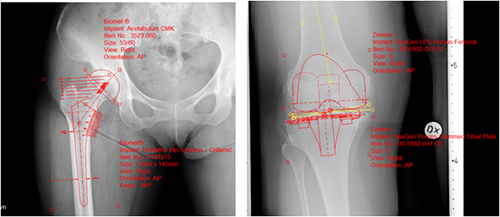

「整形外科フィルムレス・ソリューション」コーナー

”OrthoPlannerPro”は国内外メーカの豊富なインプラントデータと整形外科専門計測を搭載し,整形外科分野のスムーズな完全フィルムレスを実現。自動テンプレート配置機能,自動骨切機能等,カスタマイズ可能な計測フローにより迅速かつ正確な整形外科のプランニングフローに対応したソリューションを提供します。

- 整形外科デジタル・プランニングツール“OrthoPlannerPro”